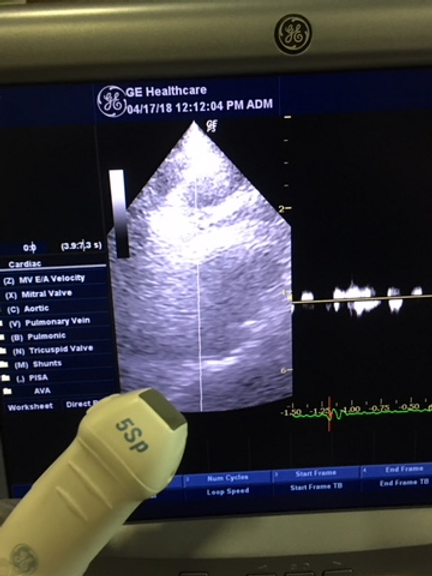

Unrivaled Imaging Capability: From gynaecology/obstetrics to urology, cardiology, and paediatrics, the LOGIQ P5 delivers exceptional 3D/4D imaging across a range of medical specialties. With its advanced features, it stands as the most powerful system in its price range, offering unmatched diagnostic precision and clarity.

Feature-Rich Performance: Enjoy access to premium features typically found on more expensive devices, including CrossXBeam composite imaging, cardiac imaging, and speckle reduction. The LOGIQ P5 sets a new standard for affordability without compromising on performance.

- Premium features including CrossXBeam composite imaging and cardiac imaging